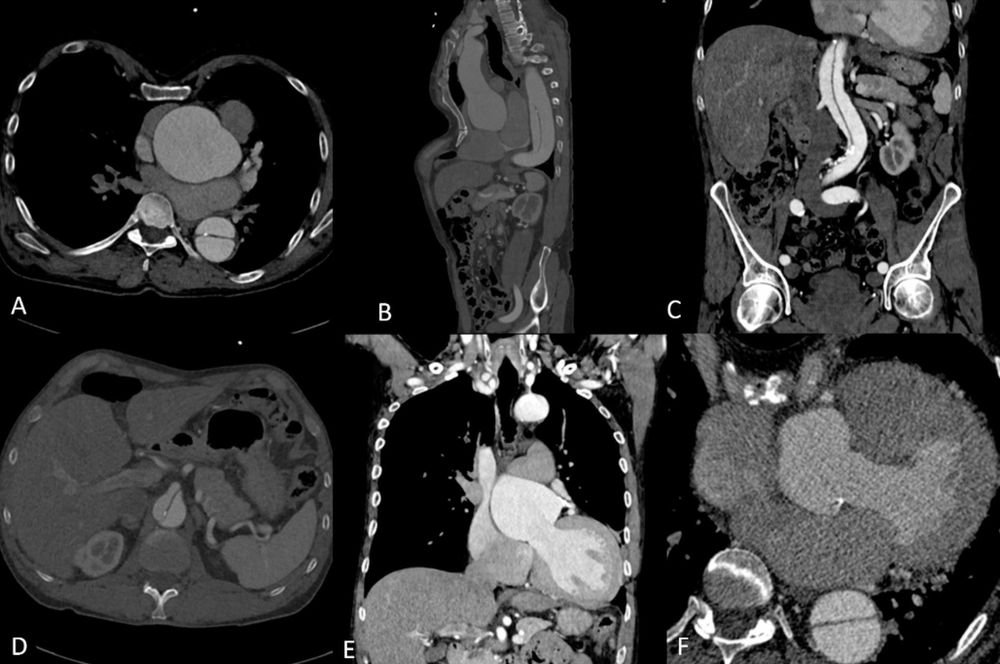

🫀 Reveal single-energy MAR algorithm effectiveness in #YesCCT for contrast-enhanced #YesCCT with EVAR/coils at #IJCVI!

🌐

Effectiveness of single-energy metal artifact reduction algorithm in CT: application to contrast-enhanced CT with EVAR and coil embolization

The International Journal of Cardiovascular Imaging - This study aimed to evaluate the efficacy of the single-energy metal artifact reduction (SEMAR) algorithm in reducing metal artifacts and...

doi.org